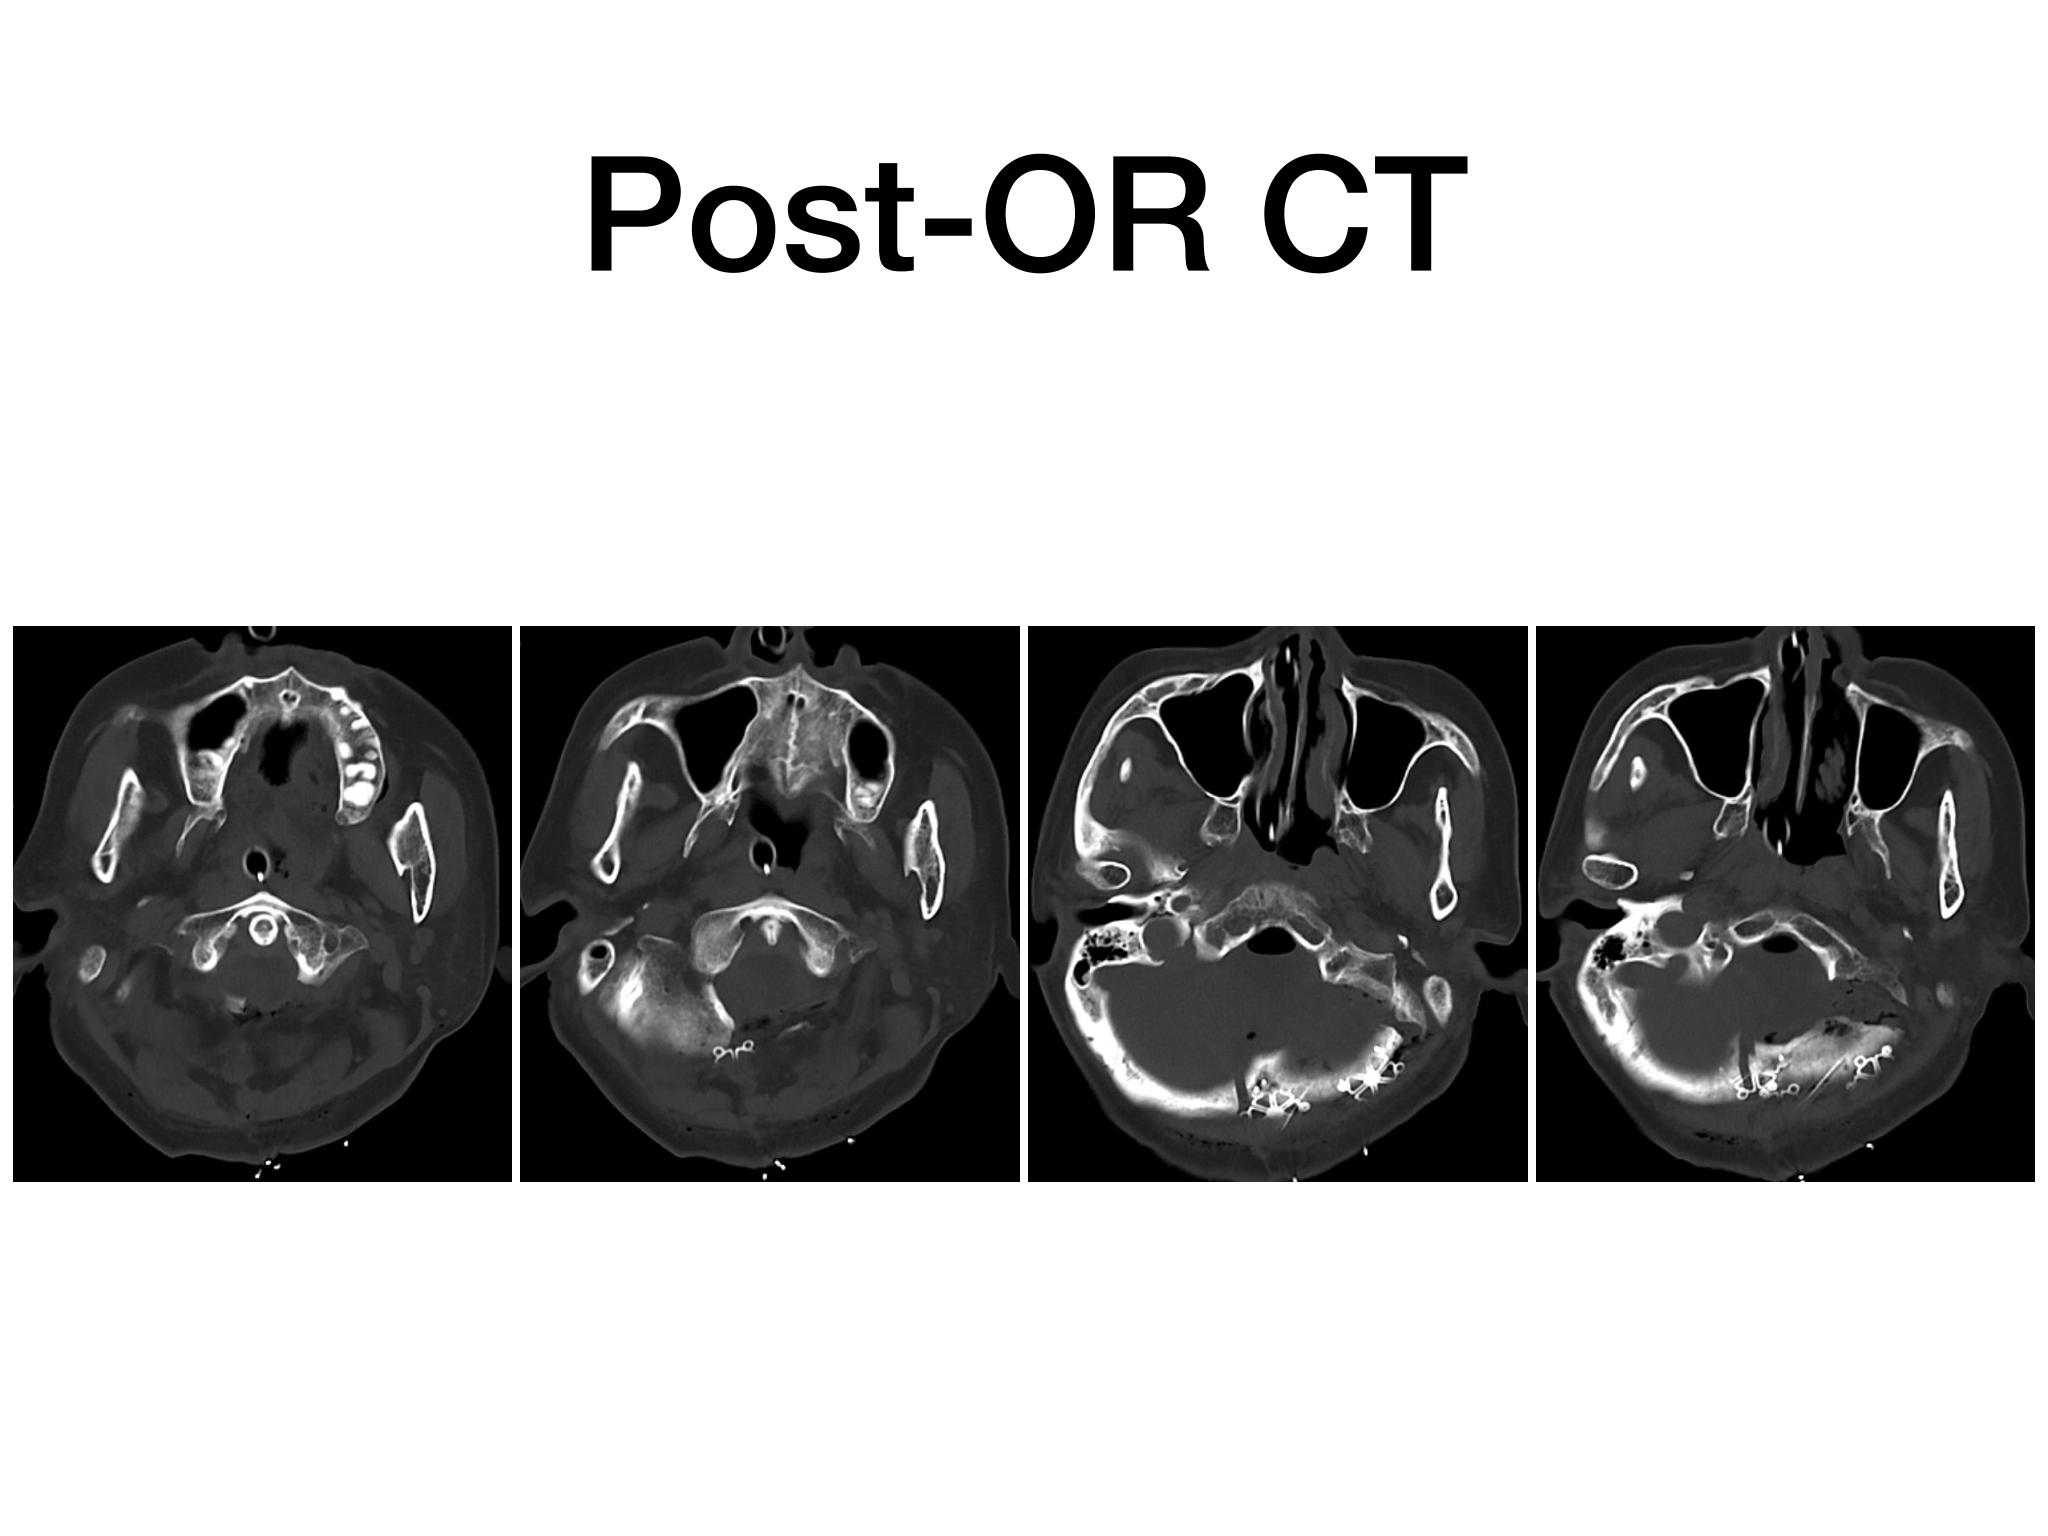

汇报一例后颅底肿瘤手术。为枕骨大孔巨大腹侧型脑膜瘤,该患者高龄,同时合并肺Ca,术前2周急性加重,枕骨大孔疝前期表现,术前已有延髓压迫及后组颅神经麻痹表现。经详细评估后采用远外侧经髁窝入路,最大化显露,重点保护延髓、后组颅神经,尽可能“零骚扰”。术中肿瘤质地韧,血供一般,与肿瘤上极与后组颅神经黏连紧密,最终99%切除,残留约1%,术后顺利康复出院,无新发症状,为后续进行肺部病变化疗创造有利条件。